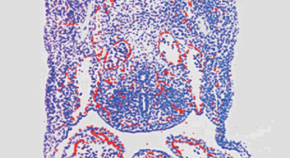

Evidence for a single microRNA (miRNA) that can efficiently differentiate multipotent stem cells into a specific lineage or regulate direct reprogramming of cells into an alternative cell fate has been elusive. Two miRNAs, miR-145 and miR-143, are now shown to be co-transcribed in multipotent cardiac progenitors before becoming localized to smooth muscle cells. miR-145 was found to be necessary for myocardin-induced reprogramming of adult fibroblasts and sufficient to induce differentiation of multipotent neural crest stem cells.